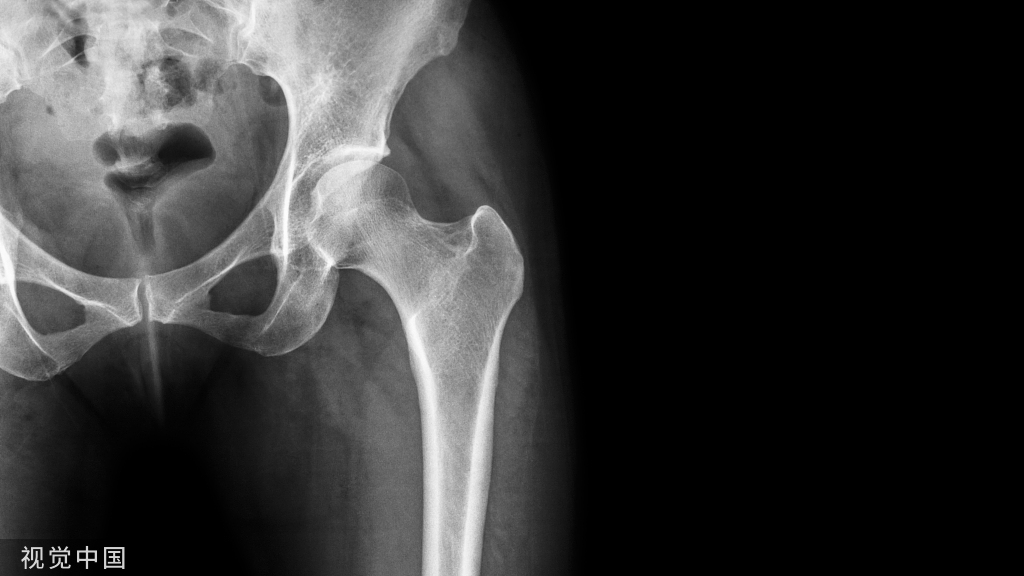

布鲁氏菌病脊柱炎的影像学表现

1、x线平片、超声检查、计算机断层扫描(CT)、磁共振成像(MRI)和骨扫描(ECT)等技术,是用于诊断骨关节布鲁氏菌病的影像学方法。2、布鲁氏菌性脊柱炎好发腰椎,以L4发病率最高;3、典型的布鲁氏杆菌性脊柱炎影像学征象,出现在感染开始后的3~5周;4、表现为椎体局灶性破坏,病灶位于椎体前部,累及上、下椎体角;5、弥漫性椎间盘塌陷,称为布鲁氏骨骺炎,是布鲁氏菌病的特异性征象;6、病灶周围骨形成和椎体终板前端骨赘形成,是典型布鲁氏杆菌脊椎炎表现。

布鲁氏菌病性脊柱炎的X线表现与诊断价值

布鲁氏菌病性脊柱炎的X线表现基本X线表现病灶呈多灶性,边缘型骨质破坏最常见,椎体变形不明显,死骨不明显。

早期表现 1、局限于椎体边缘型骨质破坏最常见,病灶呈多发、灶性、骨质疏松小病灶,多侵害1~2个椎体上缘,少数为3个椎体。数周后出现骨质缺损,呈软组织密度,无死骨,边缘清晰锐利,呈不规则虫蚀状或“刀锯”样破坏。较大的病灶呈“岛屿”状。2、布鲁氏菌侵犯椎间盘早期表现为椎间隙狭窄,密度增高,但椎体终板无破坏倾向。3、早期布鲁氏菌病性脊柱炎影像学征象,明显晚于临床症状的出现,单凭X线平片的表现,较难做出正确诊断。

1、X线平片对于布鲁氏菌病脊柱炎的诊断检查具有快速、费用低,可观察整体骨结构改变、椎间隙变窄程度及病变范围。但敏感性较低,特别早期诊断意义不大。2、有研究显示,尽管X线改变可作为诊断标准之一,但早期放射线改变并不具有特异性,一般3个月后在X线平片中出现明显改变。3、布鲁氏菌病性脊柱炎的临床症状和常规X线检查,与脊椎结核和其它骨感染有许多相似表现,易导致误诊和延误治疗。

布鲁氏菌性脊柱炎早期X线表现 边缘型骨质破坏最常见,L4/L5椎体前缘呈侵蚀样骨破坏。

布鲁氏菌性脊柱炎早期X线表现 L3/L4椎间隙狭窄,上下椎体终板及椎体边缘不规则。